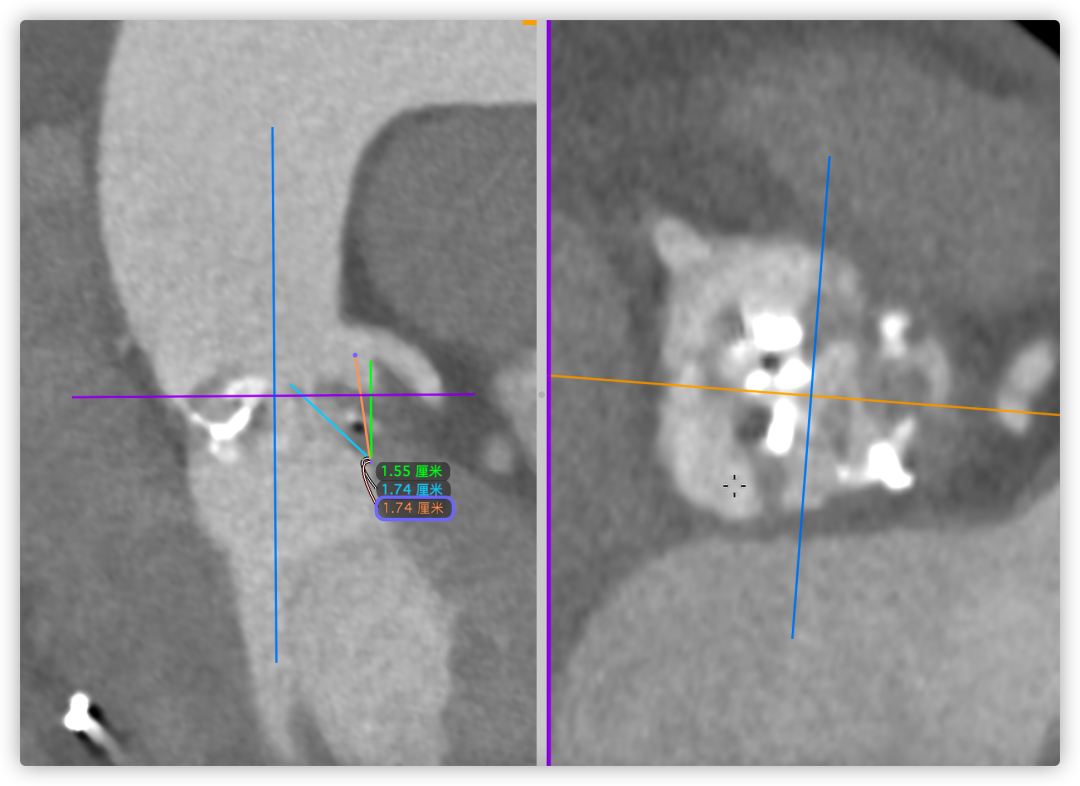

主动脉根部CT断层

根部角度/瓣环/左室流出道

瓣上结构2,4,6,8,10,12mm

SOV/STJ/AAO

左冠风险评估

间隔膜部